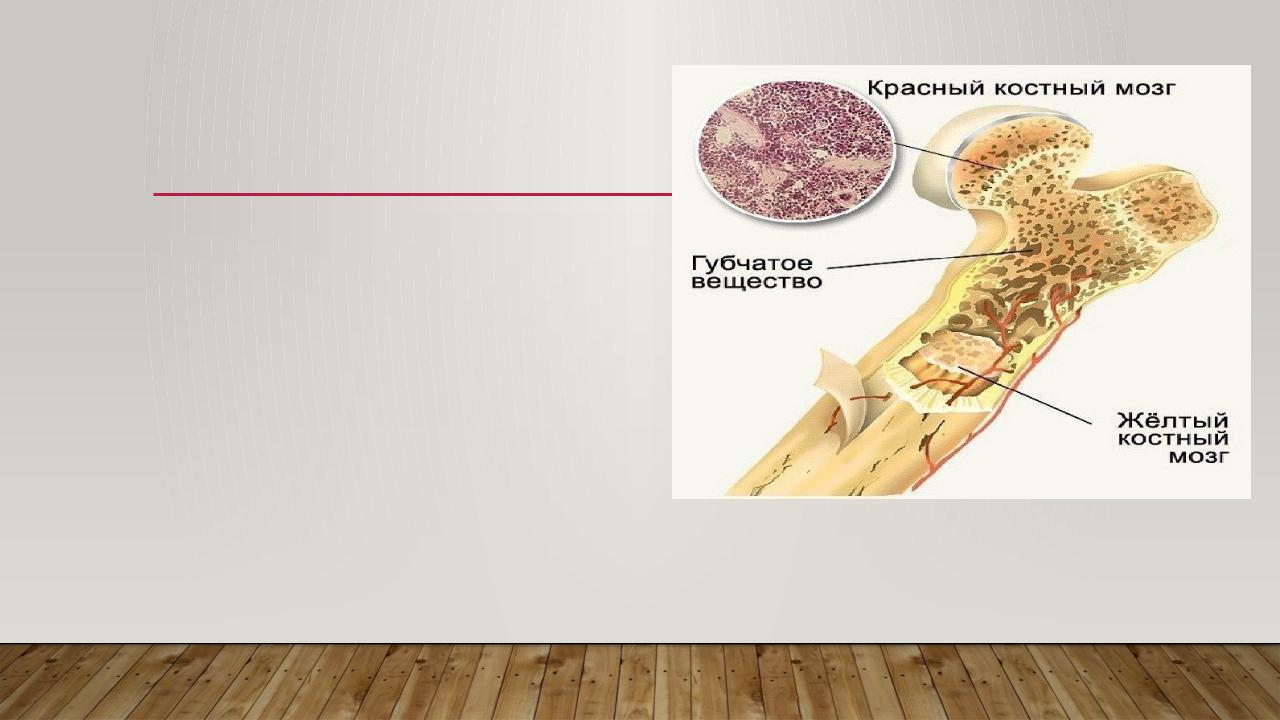

Изучение костного мозга: анатомия и функции